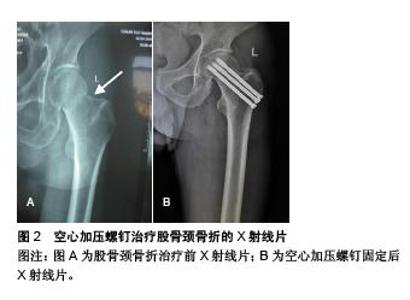

The choice of hip fracture implants and their complications

RESULTS AND CONCLUSION: Totally 20% of patients with hip fracture will have complications. Some of these are medical, and other relate to the surgical treatment itself. Our review expounded the two aspects of hip fracture implant complications according to different clinical classification of hip fracture. On one hand, the common complications of hip fracture surgery were explained by taking the commonly used implants in hip fracture surgery as the breakthrough point; on the other hand, the implant complications of hip fracture were explained by taking the fracture site as the breakthrough point. Common complications related to hip fracture implants were hip varus, joint dislocation, implants exit or femoral head cutting. Early surgical internal fixation, anti-thromboembolic and anti-infective prophylaxis, perioperative pain management, timely detection and control of delirium, correct urinary tract management, avoidance of malnutrition, vitamin D supplementation, osteoporosis treatment and the improvement of early functional activities are basic recommendations for an optimal maintenance of hip fractured patients. In recent years, with the increasing improvements of internal fixation technology and post-operative management, as well as early rehabilitation intervention, more scholars advocate in an early internal fixation treatment, so as to accelerate the functional recovery of patients’ hip joint and prevent further falls.